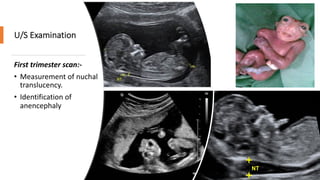

U/S Examination

First trimester scan:-

• Measurement of nuchal

translucency.

• Identification of

anencephaly